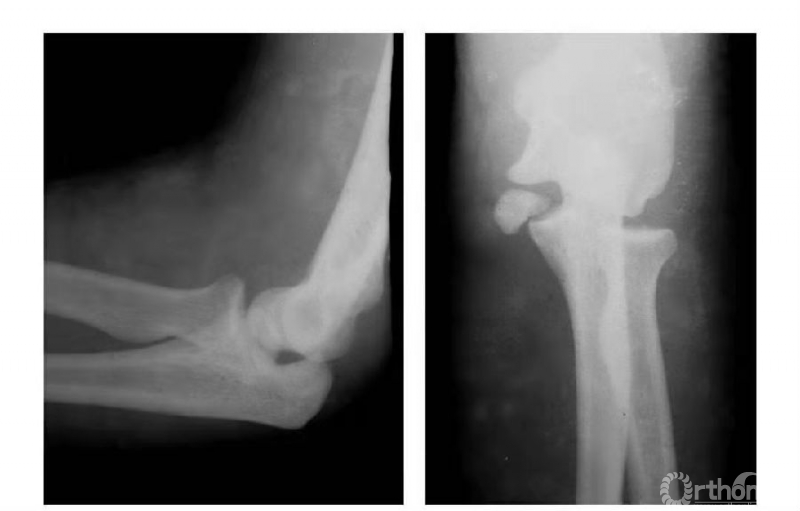

例1:肱骨内髁骨折,折线由滑车外缘沿鹰嘴窝上缘,并呈直角状而拐向内上髁(属于稳定型)(图1)。

图1

例2:肱骨内髁骨折,折线经滑车外缘斜向内髁上部(非稳定型)(图2)。

图2